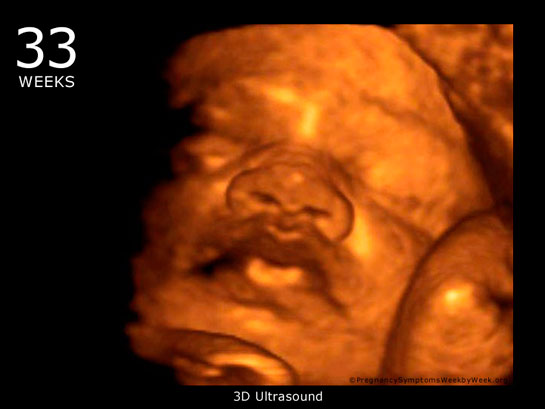

24 Haftalık Gebelik 24 haftalık gebelik, bir hamilelik sürecinin ikinci trimesterinin sonlarına yaklaşan bir dönemi temsil eder. Bu dönem, hem anne hem de bebek açısından önemli fizyolojik değişimlerin yaşandığı bir süreçtir. Bu yazıda, 24 haftalık gebelik döneminde meydana gelen gelişmeler, sağlık önerileri ve dikkat edilmesi gereken noktalar detaylı bir şekilde ele alınacaktır. Fetal Gelişim 24 haftalık gebelikte fetusun gelişimi önemli bir aşamaya ulaşmıştır. Bu dönemde, fetusun boyu yaklaşık 30 cm, ağırlığı ise 600-700 gram civarındadır. Aşağıda, fetal gelişim ile ilgili bazı önemli noktalar belirtilmiştir:

Bebek Gelişimi